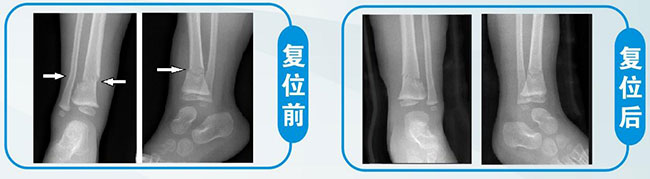

8、 儿童踝部骨折